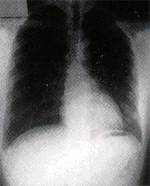

正 常 心 臟 |

心 肌 肥 厚 或 放 大 |